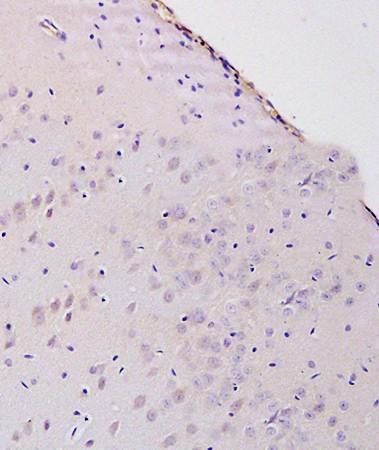

IHC-P of rat brain tissue(Normal)(8-Hydroxy-2-deoxyguanosine antibody at 1:300)